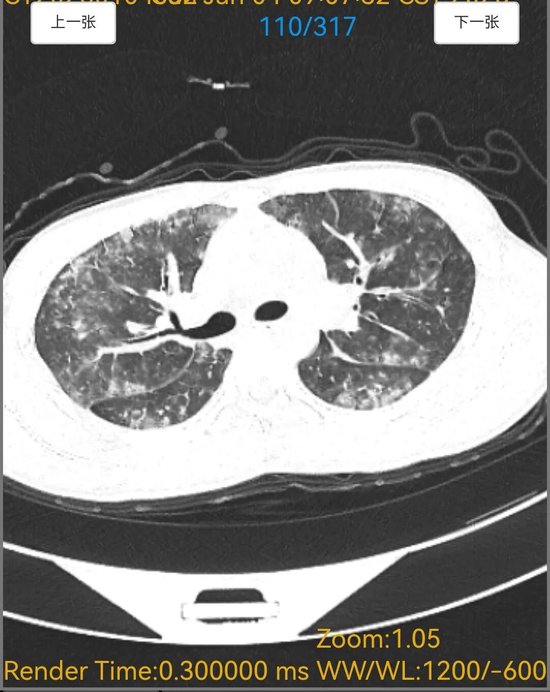

6天胸闷气短、5天持续高热,18岁的小宋被紧急送入平原县人民医院呼吸内科,胸部CT检查结果让接诊医生忧心不已,双肺布满大片“毛玻璃”阴影,呈现弥漫性病变,提示肺部正遭受严重侵袭。更棘手的是,常规感染筛查中,细菌、病毒等常见病原体检测均为阴性,病因成谜,治疗陷入困境。

诊断明确后,呼吸内科医师团队制定了针对性极强的精准治疗方案。令人惊叹的疗效随之出现,在针对性药物治疗仅5天后,患者复查胸部CT。影像对比显示,原本遍布双肺的弥漫性“毛玻璃”阴影已基本完全吸收